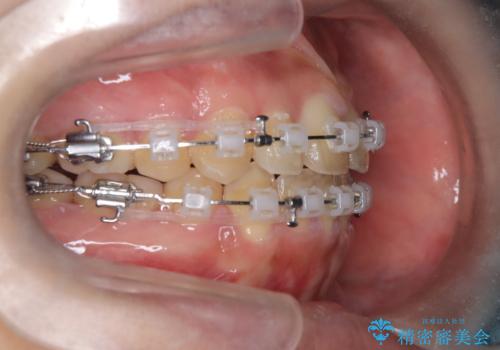

【抜歯矯正】クリア装置で1年半

- 矯正装置

- クリア装置

- 1年6ヶ月

クリア装置とは、当院において最も摩擦を減らした装置のため比較的動きが早く治療がスムーズに進みます。